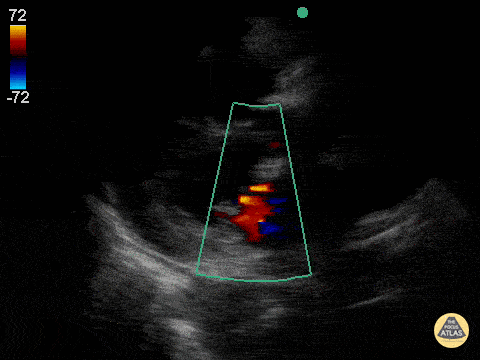

This was a patient who presented at the age of 98 who had become progressively more short of breath over the last several months and now had trouble getting around. Very sharp and witty woman, who wished to have no aggressive measures. She was tucked into the cardiology service for gentle diuresis and optimization of her heart disease. This parasternal long axis demonstrating alternating mild-moderate aortic regurgitation with moderate mitral regurgitation. Jason Tanguay, DO